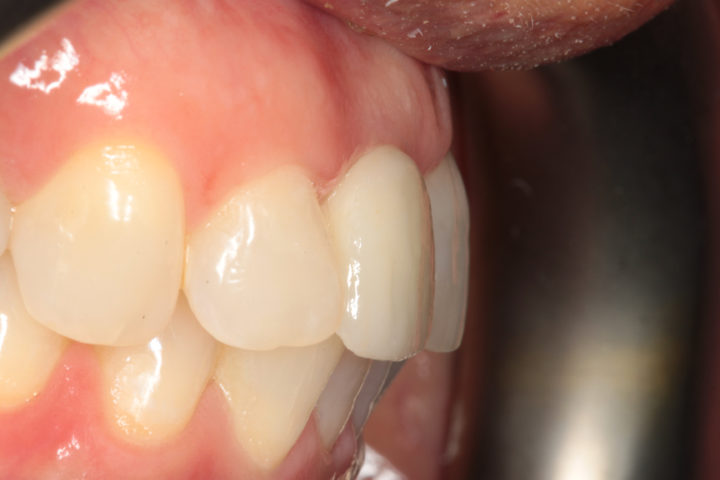

Risultato frontale:

Dopo l’intervento di implantologia, il nuovo incisivo su impianto si integra perfettamente per forma, colore e funzione. Il sorriso risulta naturale, armonico e completamente riabilitato.